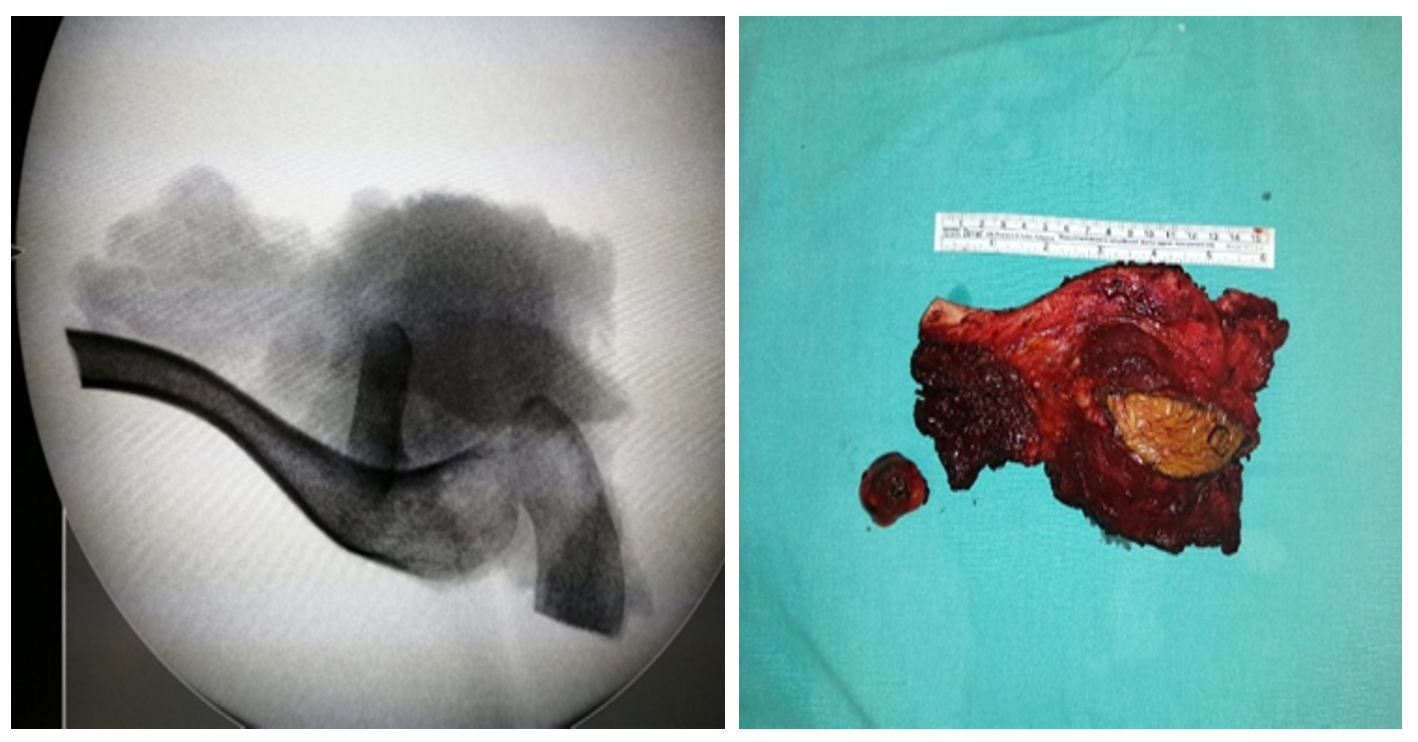

Ameliyat Esnası: Çıkarılan tümör dokusunun skopi ve klinik görüntüsü.